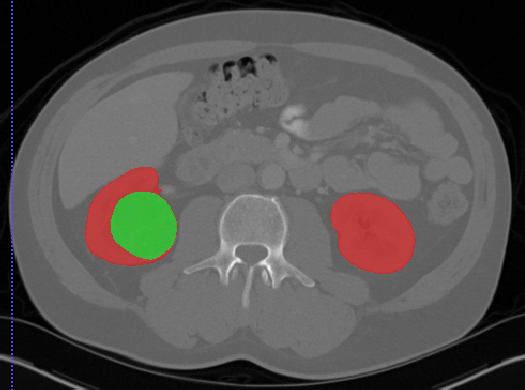

Edge-Aware 3D Image Segmentation Networks

[91]: Automated segmentation of kidneys and kidney tumors is an important step in quantifying the tumor’s morphometrical details to monitor the progression of the disease and accurately compare decisions regarding the kidney tumor treatment. Manual delineation techniques are often tedious, error-prone and require expert knowledge for creating unambiguous representation of kidneys and kidney tumors segmentation. We propose a 3D end-to-end edge-aware FCN for reliable kidney and kidney tumor semantic segmentation from arterial phase abdominal 3D CT scans. Our segmentation network consists of an encoder-decoder architecture that specifically accounts for organ and tumor semantics. We evaluate our model on the 2019 MICCAI KiTS Kidney Tumor Segmentation Challenge dataset. -

Kidney and Kidney Tumor Segmentation

Kidney cancer accounted for nearly 175,000 deaths worldwide in 2018 [13], and it is projected that 14,770 deaths will occur due to the disease in 2019 in the US [111]. Current kidney tumor treatment planning includes Radical Nephrectomy (RN) and Partial Nephrectomy (PN). In RN, both the tumor and the affected kidney are removed whereas in PN the tumor is removed but kidneys are saved [116]. Although RNs were historically prevalent as a standard treatment procedure for kidney tumors, new capabilities for earlier detection of the tumors as well as advancements in surgery has made PNs a viable treatment approach [53].

Traditionally, various techniques such as deformable models [86], GrabCuts, region growing and atlas-based methods have been applied to the problem of kidney segmentation. In recent years, researchers have attempted to leverage the power of deep learning and CNNs to build segmentation frameworks that are more automated and less dependant on incorporation of prior shape statistics. Thong et al. [119] proposed a 2D patch-based approach for kidney segmentation in contrast-enhanced CT scans by leveraging a modified ConvNet.

Jackson et al. [62] developed a framework for detection and segmentation and of kidneys in non-contrast CT images by utilizing a 3D U-Net. Yang et al. [128] proposed a method for kidney and renal tumor segmentation in CT angiography images by a modified residual FCN that is equipped with a pyramid pooling module. Furthermore, Yin et al. [130] employed a cascaded approach for segmentation of kidneys with renal cell carcinoma by training a CNN that predicts a bounding box around the kidney and a subsequent CNN that segments the kidneys. Recently, Xia et al. [126] proposed a two-stage approach for the segmentation of kidney and space-occupying lesion areas by using SCNN and ResNet for image retrieval and SIFT-flow and MRF for smoothing and pixel matching.